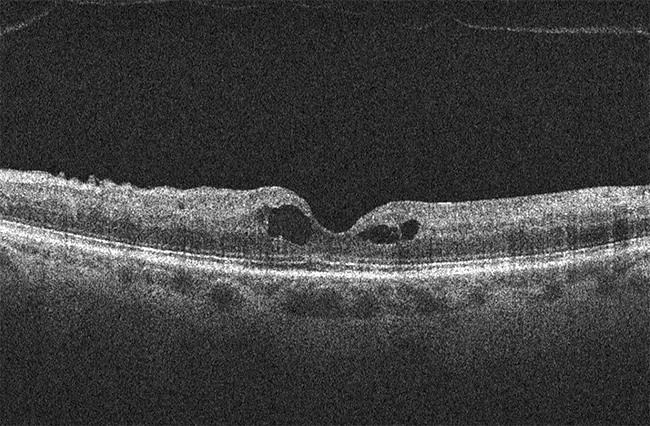

Ineens zag ik niets meer met mijn linkeroog. Het bleek dat ik een oogtrombose had. Een bloedvat achter mijn oog was gesprongen. Heb ik weer!